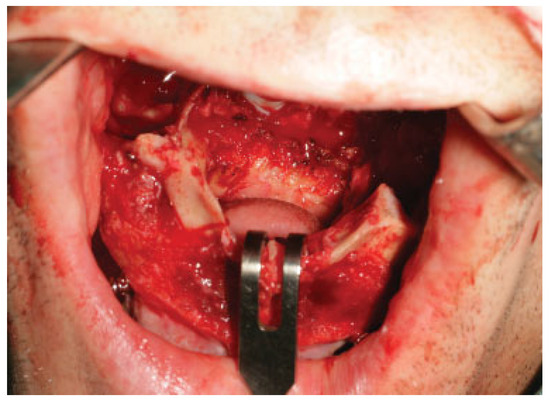

Orbitozygomatic fractures are one of the most common maxillofacial injuries encountered. This study aims to investigate and review the management and complications of orbitozygomatic fractures at the Royal Brisbane and Women’s Hospital (RBWH). Specif...